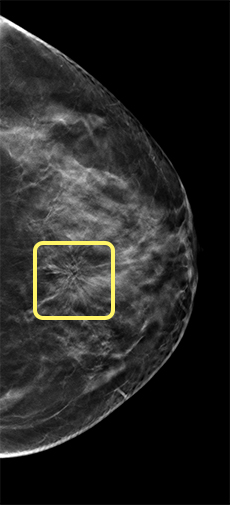

The research team reviewed 2.3 million breast-screening exams collected by the national Breast Cancer Surveillance Consortium, making it the largest-ever study of U.S. access to digital breast tomosynthesis (DBT), commonly called 3D mammography. In February 2011, the Food and Drug Administration approved DBT as an alternative to digital mammography, then the standard of care. Subsequent observational studies have shown that DBT is more accurate than digital mammography by detecting more cancers and yielding fewer false-positive readings.

In 2011, only 3% of women in the study could access DBT at the time of their screening; by 2017, that figure had grown to 82%. Despite facilities’ adoption of 3D technology over those seven years, the improved availability was not experienced equally.

When both 2D and 3D mammograms were available onsite at time of screening, DBT was obtained by:

- 37% of Black women vs. 43% of Asian-American women, 44% of Hispanic women, and 53% of white women

- 41% of women with less than a high school education vs. 50% of women with a college degree

- 44% of women living in zip codes with the lowest quartile of median household income vs. 51% of women living in zip codes with the highest quartile of median household income